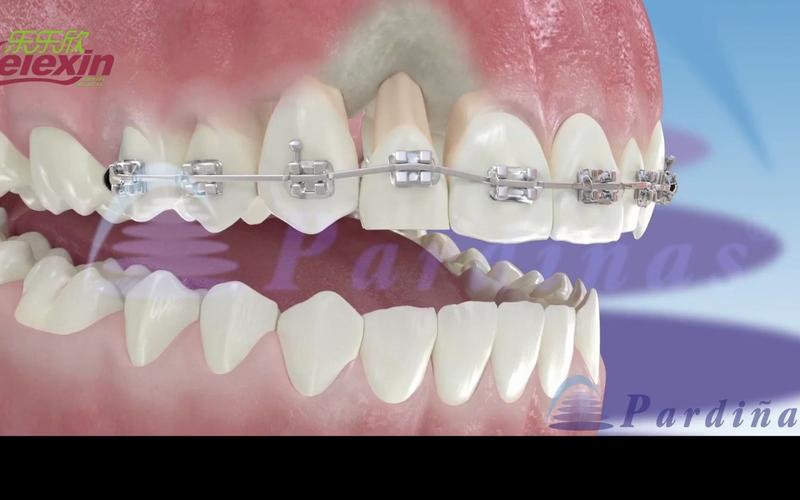

- 牵引尖牙向远中移动:牵引圈呈“Ω”形,主体直径略大于尖牙牙冠宽度,牵引钩指向远中。

- 关闭前牙间隙:牵引圈为椭圆形,长轴与牙弓一致,牵引钩位于侧牙近中。

- 弯制圆形主体:保持钢丝与钳口垂直,细丝钳钳尖沿折角方向旋转,同时向内施加压力,弯制半圆弧(约180°);翻转钢丝,对称弯制另一侧半圆,形成完整圆形。

- 调整对称性:用卡尺测量主体直径,若两侧不对称,用梯形钳轻柔调整弧度,确保圆周均匀。

- 调整弧度贴合度:将弯制好的牵引圈放在模型或石膏牙上,检查是否与牙冠表面贴合,避免压迫牙龈乳头;若不贴合,用细丝钳轻柔调整主体弧度,直至牵引圈能稳定套入牙冠且无翘动。

- 修整牵引钩方向:用梯形钳调整牵引钩角度,确保牵引力方向与牙齿移动方向一致(如牵引尖牙远中移动,牵引钩应指向远中偏龈方)。